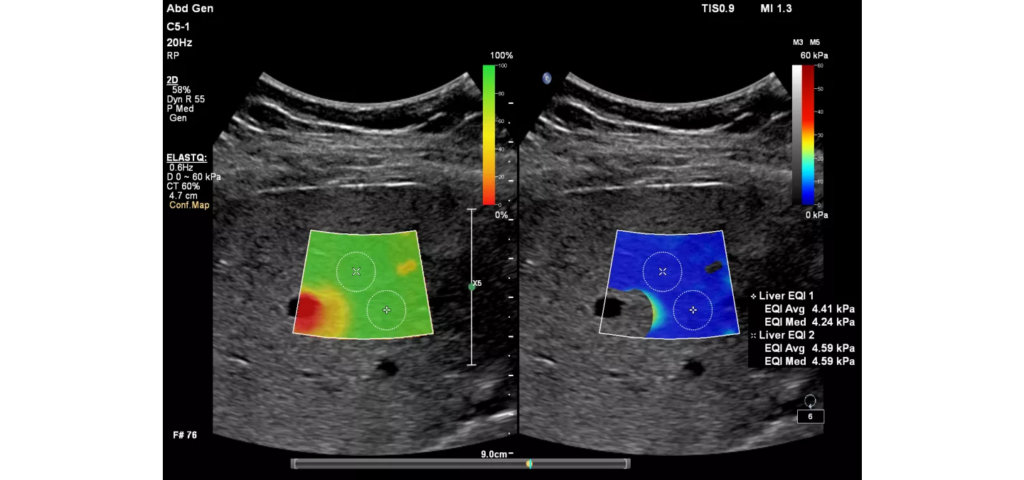

Philips EPIQ Elite ultrasound features an exceptional level of clinical performance, workflow, and advanced intelligence to meet the challenges of today’s most demanding practices. The EPIQ Elite platform brings ultimate solutions to ultrasound, with clinically tailored tools designed to elevate diagnostic confidence to new levels.